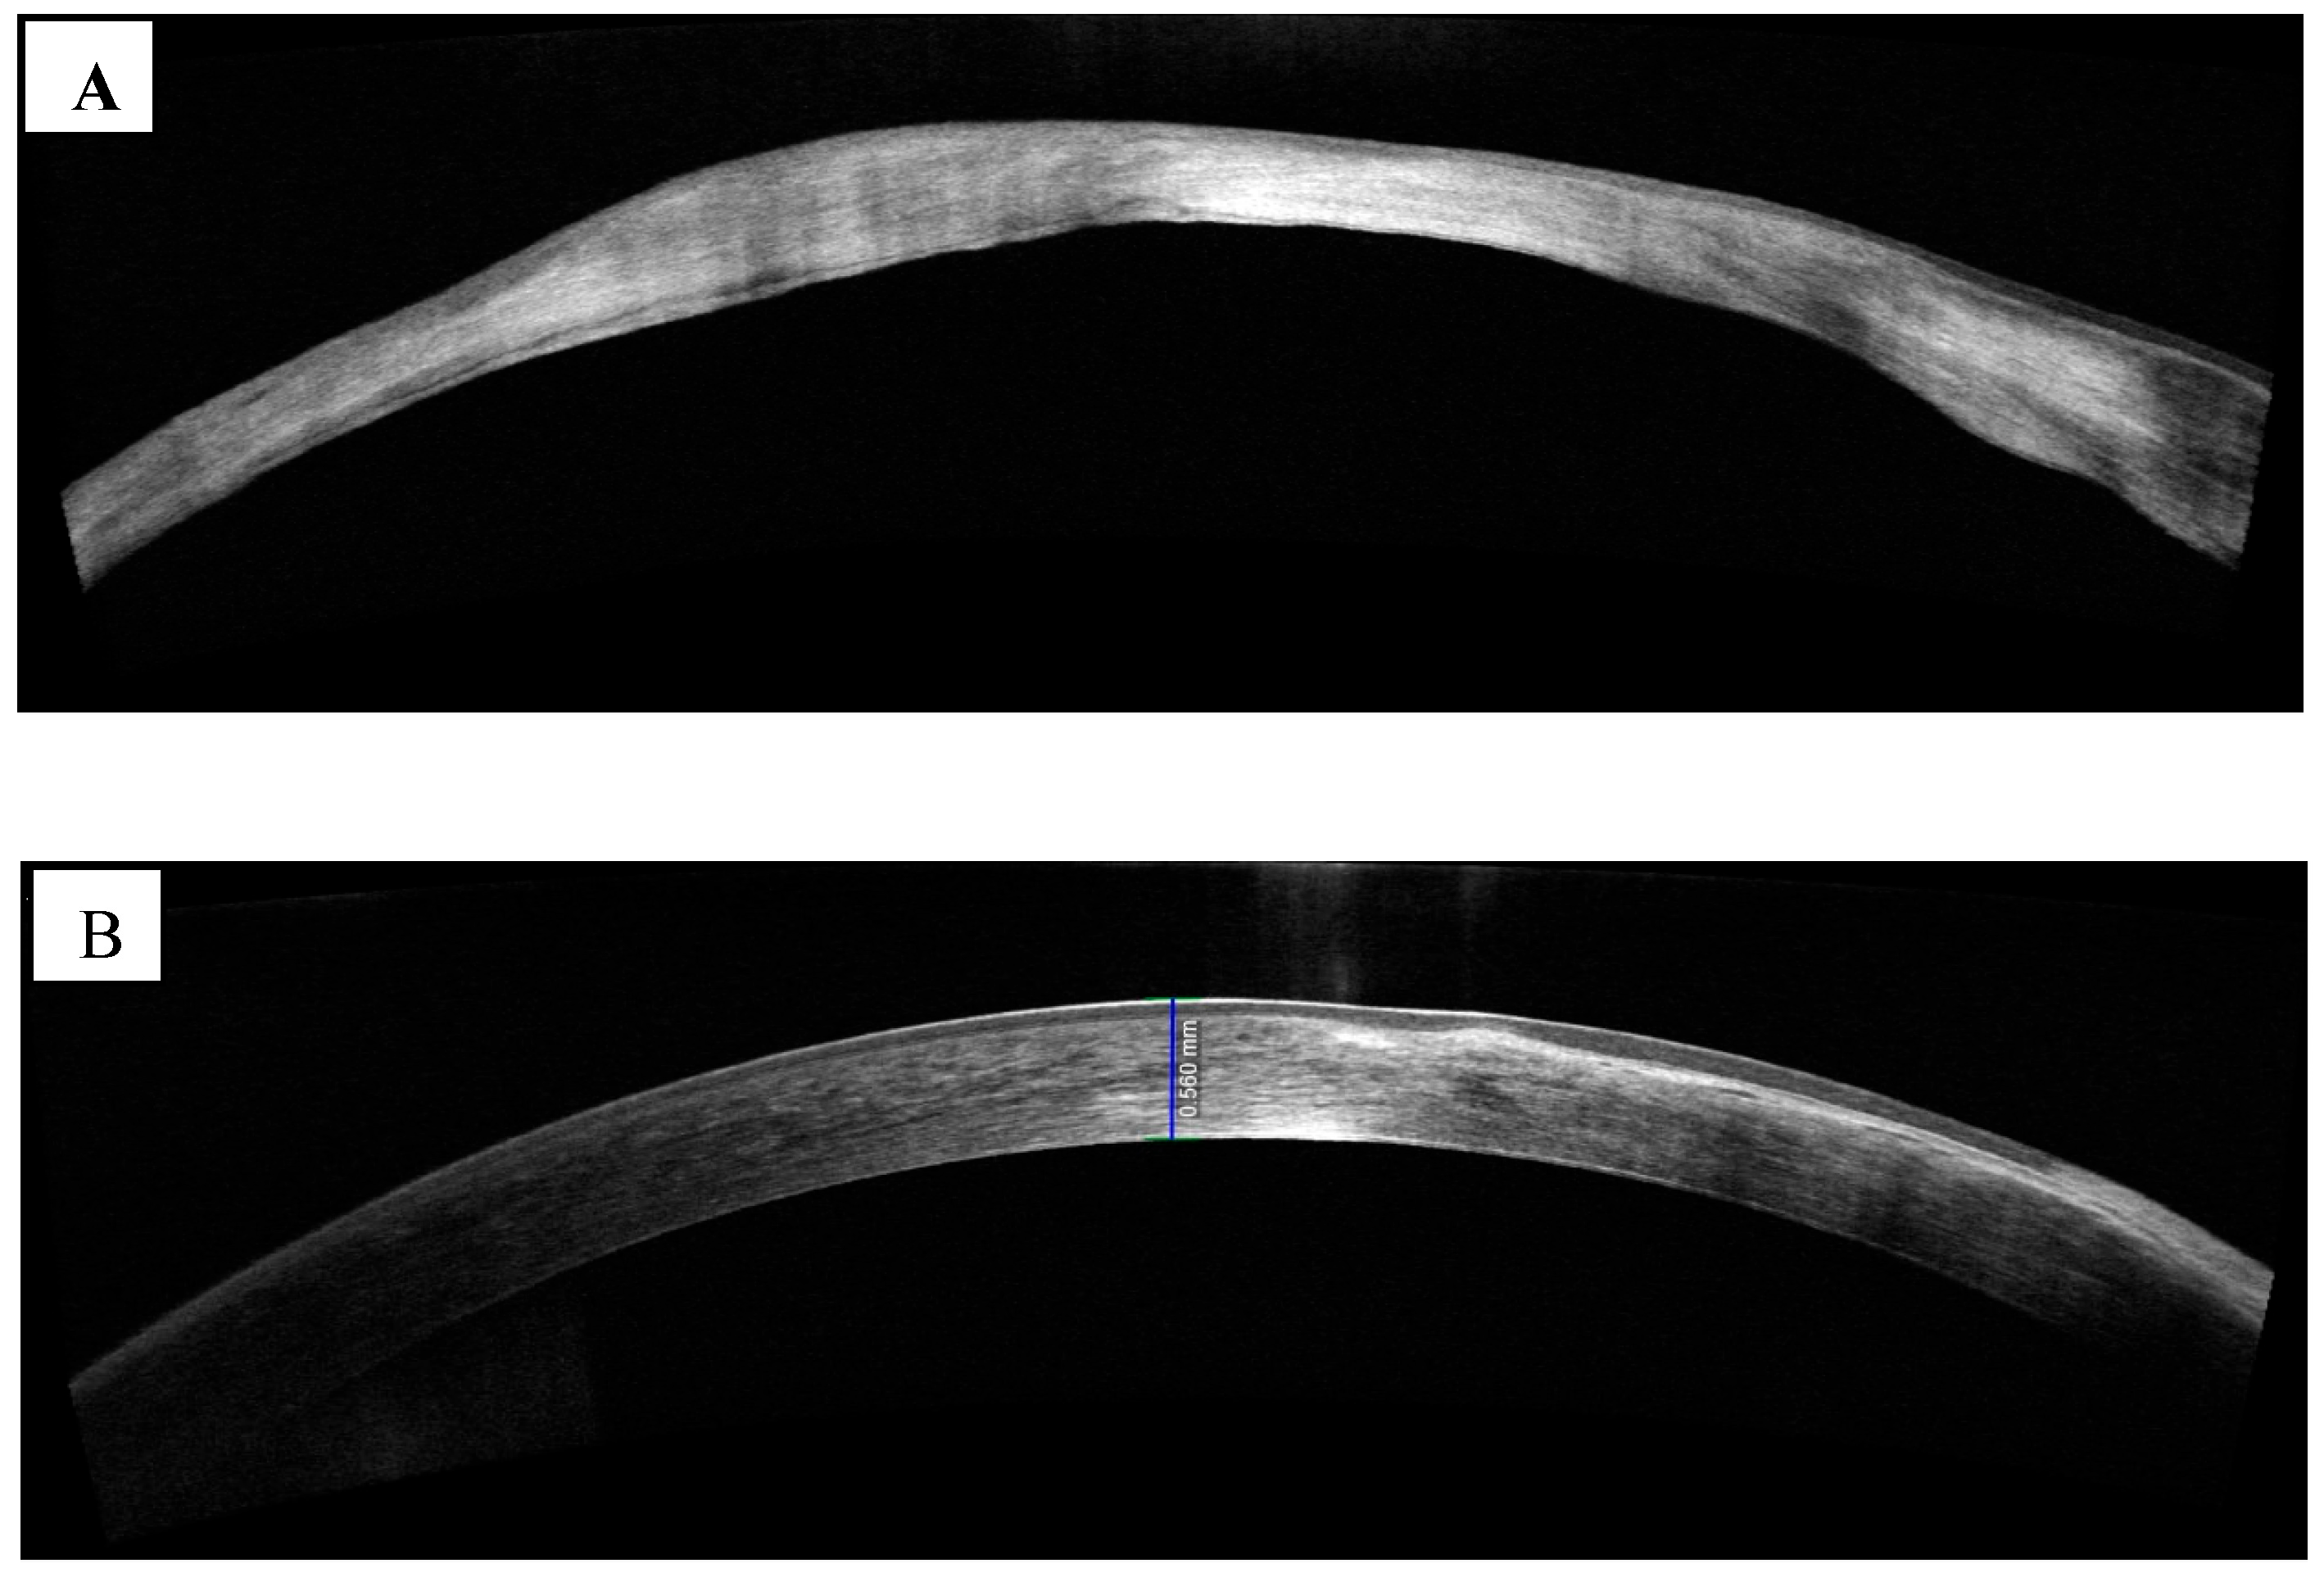

- Konstantopoulos, A.; Yadegarfar, G.; Fievez, M.; Anderson, D.F.; Hossain, P. In vivo quantification of bacterial keratitis with optical coherence tomography. Invest. Ophthalmol. Vis. Sci. 2011, 52, 1093–1097. [Google Scholar] [CrossRef]

- Soliman, W.; Fathalla, A.M.; El-Sebaity, D.M.; Al-Hussaini, A.K. Spectral domain anterior segment optical coherence tomography in microbial keratitis. Graefe’s Arch. Clin. Exp. Ophthalmol. 2013, 251, 549–553. [Google Scholar] [CrossRef]

- Oliveira, M.A.; Rosa, A.; Soares, M.; Gil, J.; Costa, E.; Quadrado, M.J.; Murta, J. Anterior segment optical coherence tomography in the early management of microbial keratitis: A cross-sectional study. Acta Med. Port. 2020, 33, 318–325. [Google Scholar] [CrossRef]